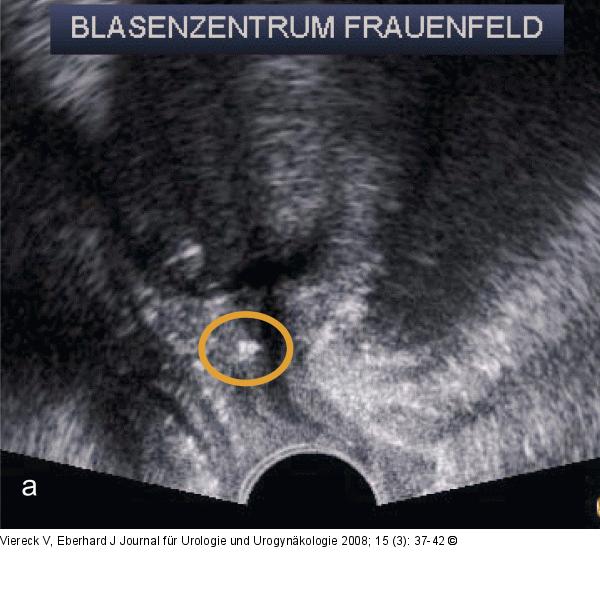

Abbildung 4a-b: Introitussonographie Eine zu hohe Bandspannung zeigt im Ultraschall (Introitussonographie) bereits in Ruhe eine Krümmung (C-Form) des Bandes (a), im Stressprofil resultiert daraus ein massiver Druckanstieg (Quetschhahnmechanismus) (b). |

Eine zu hohe Bandspannung zeigt im Ultraschall (Introitussonographie) bereits in Ruhe eine Krümmung (C-Form) des Bandes (a), im Stressprofil resultiert daraus ein massiver Druckanstieg (Quetschhahnmechanismus) (b). |